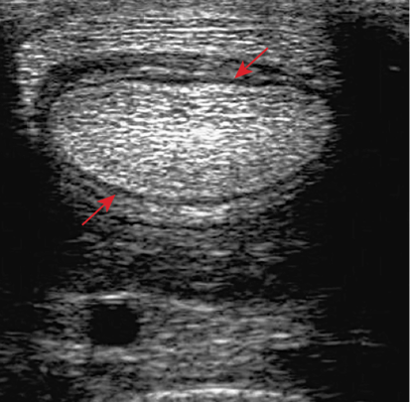

Upon further examination, contrast radiographs and ultrasound scans failed to identify any significant abnormalities apart from swollen synovium within the DFTS. To address this issue, our veterinary team administered 5mg of triamcinolone acetonide along with 20mg of HA, complemented by a compression wrap. Subsequently, the horse underwent a two-week confinement period in a small yard, followed by gradual reintroduction to exercise through 10 minutes of hand walking twice daily, with the distal limb wrapped for additional support.